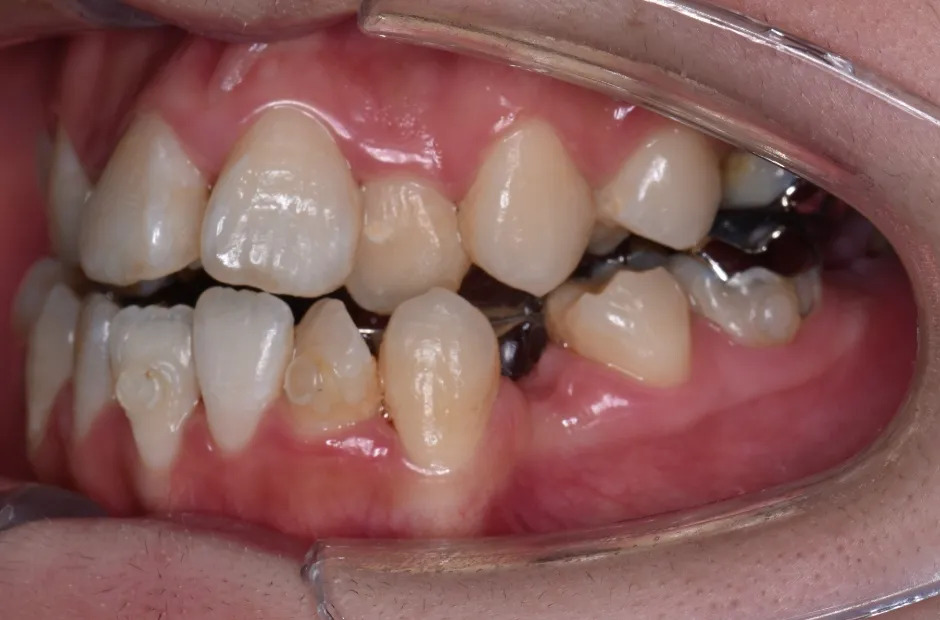

八重歯・でこぼこ・乱ぐい歯

(叢生)

歯が並ぶスペースが足りないために、歯が重なったり前後にずれて生えていたりする状態です。犬歯(八重歯)など目立つ部分の歯列が乱れている場合は、口元の印象に悪影響を与えます。原因としては、遺伝や乳歯の早期抜歯、顎の成長不足などがあげられます。歯磨きが不十分になりやすく、虫歯や歯周病のリスクが高まりやすい不正咬合です。矯正治療を受けると、見た目がよくなるだけでなく清掃性が高まり、お口の健康を維持しやすくなります。

| 診断名・主訴 | 下顎前突、叢生 |

|---|---|

| 年齢・性別 | 23歳・女性 |

| 治療期間・回数 | 3年 |

| 治療に用いた主な装置 | 上顎5,5 下顎4,4 |

| 抜歯部位 | 舌側矯正 |

| 治療費 | 100万円(税抜) |

| リスク・副作用 | 装置による違和感・疼痛・歯肉退縮・歯根吸収・虫歯のリスクなど |

治療中